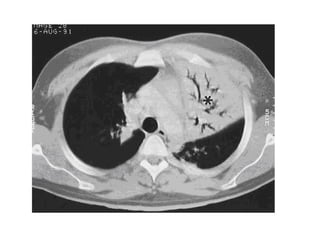

LIP in a 47-year-old woman, high-resolution CT image shows diffuse

ground-glass opacity (arrow) with multiple perivascular cysts

(arrowheads) and reticular abnormalities (*)